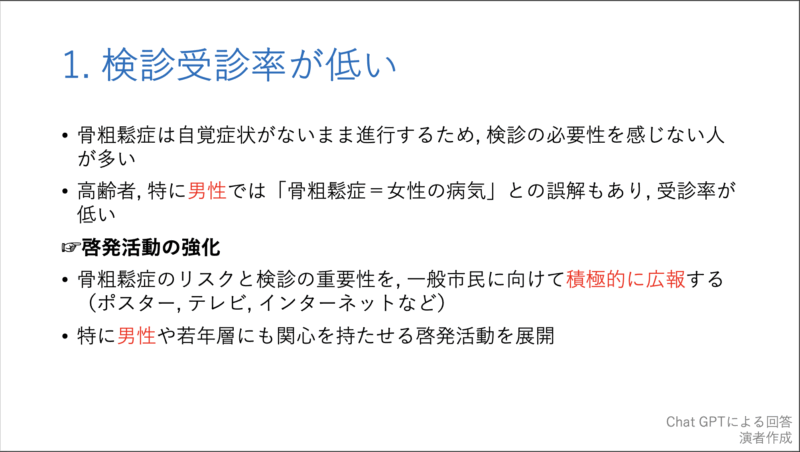

20時過ぎから, 私がclosing remarksとして, 10分で骨粗鬆症検診の問題点とその対策, および各県庁所在地での現状について, チャットGPTからの回答をからめてお話ししました. 途中で, 自分の大腿骨頚部骨折のことも取り上げました.